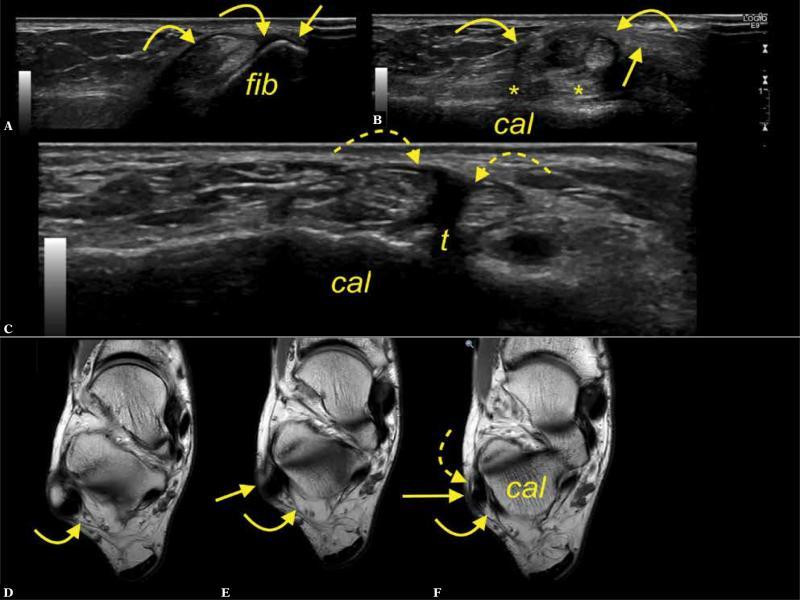

Fig. 2.

A 34-year-old patient with a suspicion of a ganglion. A, B. transverse section on ultrasound corresponding to section d. C, D, E. T2-weighted slightly oblique section. The interconnection (straight arrows) between the SPR (curved arrow) and ATFL (curved dashed arrow); fib – fibula

MR revealed this connection significantly more often than US (47.6% vs. 28.6%, p <0.001) (Tab. 1). The connection was visualized as a linear echogenic fibrous band on US, and as a narrow, low signal intensity linear strip on MR, and was often evident at the external outline of the lateral malleolus near the cortex (Fig. 3 and Fig. 4).

Fig. 3.

A 24-year-old patient with pain anterior to the lateral malleolus. A. transverse section on ultrasound, B, C. T2-weighted slightly oblique sections. The interconnection (arrows) between the SPR (curved arrow) and IER (dashed arrow); fib – fibula

Fig. 4.

A 42-year-old patient presenting clinical suspicion of synovitis. A, B, C. transverse section on ultrasound, d-proton density-weighted oblique oriented section. The interconnection (arrows) between the SPR (curved arrow) and IER (dashed arrow); fib-fibula

The IER served as an intermediate station for connecting the SPR to the ATFL in 8 cases on MRI (12.7%) and in 5 cases on US (7.9%), but the difference was not significant (p >0.05) (Fig. 3). In those cases, a direct connection between the SPR and the ATFL was also noted (n = 13, 20.6%) (Fig. 5).

Fig. 5.

A 52-year-old patient presented with retromalleolar pain. A, B, C. transverse section on ultrasound. D. proton density-weighted transverse section. The interconnection (arrows) between the SPR (letter R) and IER (curved arrow) and ATFL. Fib – fibula